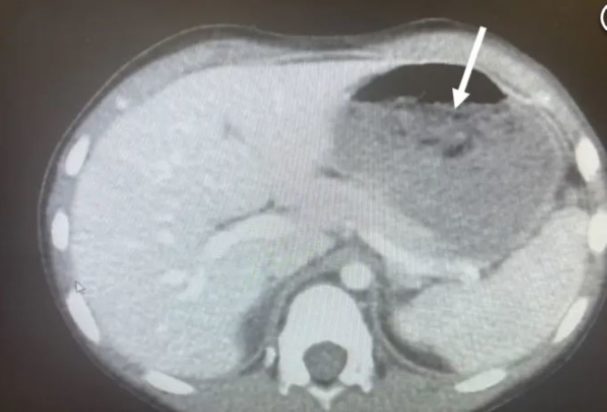

Οι γιατροί που εξέτασαν τον ανήλικο αμέσως έψαξαν για ξένα αντικείμενα στο στομάχι του, καθώς τα παιδιά συνηθίζουν να καταπίνουν αντικείμενα. Η ομάδα των γιατρών του 5χρονου εντόπισε στην ακτινογραφία μία τεράστια μάζα από τσίχλες, η οποία είχε φράξει το έντερο του παιδιού.